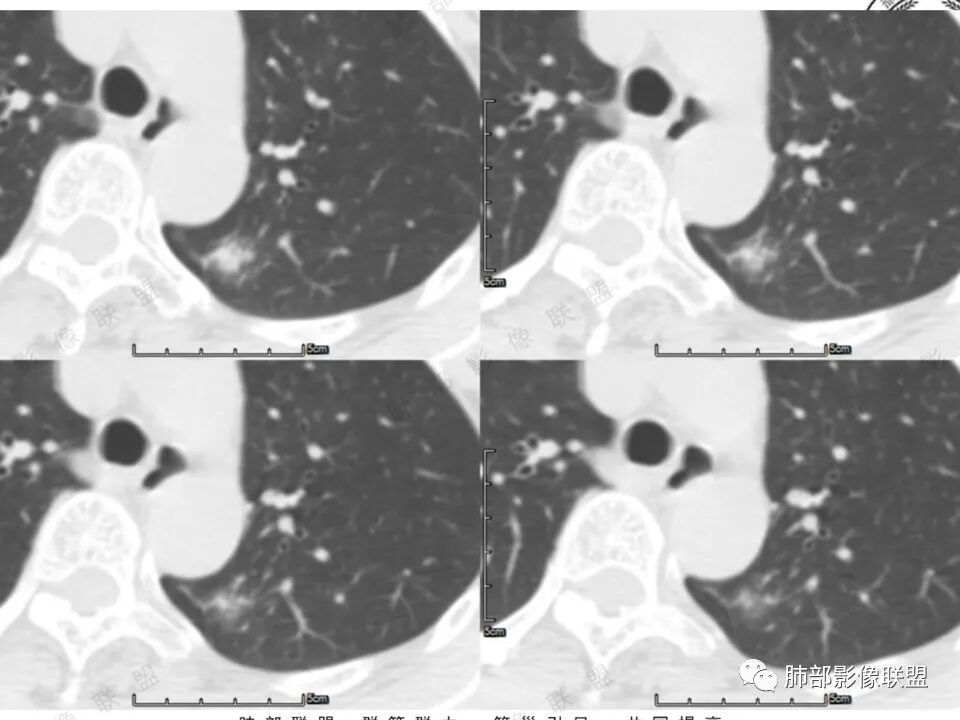

高强化,实性结节,边缘有磨玻璃,有膨隆,斜裂侧偏平直胸膜凹陷,IAC,鉴别炎性肉芽肿

左肺上叶长条状病灶,胸膜牵拉,边缘平直,磨玻璃边界清楚,不均匀强化,考虑炎性,不完全排除肺癌

左肺结节,形态不规则,边缘略收缩,分叶,部分边缘平直,周围可见清晰磨玻璃影,增强后明显强化,考虑:血管瘤,炎性假瘤,鉴别腺癌

左肺上叶尖后段病灶,毛玻璃边界不清,实性成分边缘平直,重建,病灶长条形,增强明显强化,考虑炎症

中年女,左肺结节,边缘平直,明显持续不均匀强化,周围略毛糙,考虑IMT

左肺结节,形态不规则,磨玻璃边界欠清,增强明显强化,考虑炎性,OP?IMT?,鉴别腺癌

中年女性,左肺上叶长条状病灶,宽基底与胸膜交界,胸膜凹陷,病灶边缘平直,局部收缩及膨隆,周围可见磨玻璃,其边界清楚,增强病灶不均匀强化,影像表现有炎性病变,也有明显占位表现,考虑OP,有膨胀性表现的小结节,不完全排除肺癌!需要结合相关检查。

混合磨玻璃,边界清,边缘凹陷,月牙铲,虽明显强化,还是先考虑腺癌,鉴别炎性肉芽肿或IMT等。

晨读:中年女性,体检发现,左肺上叶结节,形态不规则,呈长条状,分叶,部分边缘平直,周围可见磨玻璃影,增强后明显强化,首先考虑良性病变:1、炎性病变。2、血管瘤。

体检发现左肺上叶尖后段混合磨玻璃结节,考虑浸润性腺癌可能性大,建议抗感染后复查,明显强化有不支持的地方,左肺上叶尖后段外侧胸膜下小磨玻璃结节,提示AAH。

女,41岁,体检发现肺部结节。左肺上叶长形病灶,具有轻度膨胧感,刀切尖角征,胸膜粘连,早期强化见薄环强化征象,后期有延迟强化特点。病灶周围不是很干净。考虑结核肉芽肿或炎症肉芽肿。

中年女性,查体发现左上肺条块结节,靠近斜裂,边缘平直有收缩,胸膜牵拉,明显强化,考虑炎性假瘤或炎性肉芽肿,鉴别腺癌。

中年女性,体检发现。左肺上叶后段不规则结节灶,密度不均匀,病灶周围可以边界似清非清毛玻璃影,临近胸膜牵拉,增强扫描病灶明显不均匀强化。考虑炎性假瘤,鉴别腺癌。

混合磨玻璃,边界清,分叶,收缩力强,月牙铲,胸膜凹陷,虽明显强化,还是先考虑腺癌,鉴别炎性肉芽肿。

左肺上叶尖后段实性结节,边缘有清晰磨玻璃,胸膜有牵拉凹陷,明显强化,CT值超过主动脉,考虑血管畸形(周围磨玻璃可能是出血),鉴别IAC(影像表现符合,强化不符)

混合密度结节,磨玻璃密度边缘清楚,考虑腺癌。

患者中年女性,体检发现。胸部CT:左肺上叶后段长条形结节灶,边缘光滑,边界清楚,见分叶、毛刺、胸膜牵拉及平直征象。增强明显强化,内可见血管增粗,综合考虑恶性病变,浸润性腺癌可能大,鉴别结核。

形态特征符合腺癌,就是这个强化幅值相对少见些,肺内其他高强化病变如类癌、血管瘤等形态又不甚符合。还是常规考虑浸润腺癌吧,当然抗炎复查这个过程还是要的。

41岁女性,左肺上叶不规则结节,边缘见似清非清的磨玻璃影,叶间裂牵拉。整体病灶边缘平直,强化明显。另左上叶外侧尚有一磨玻璃结节(蘑菇兄弟?),考虑炎性肉芽肿可能性大。强化太明显让人很纠结,会不会存在CD,但边缘又有磨玻璃影;腺癌、结核、隐球都没有见过强化这么明显的,强化程度与主动脉基本一致,不会是动静脉畸形吧。

左上肺前后段不规则实性病灶,浅分叶,边缘部分平直收缩,轻微胸膜牵拉,伴周围磨玻璃样改变,强化明显,感觉是炎性恶性征像均有。

左肺上叶后段条片状影,边缘部分模糊,前缘平直后缘澎隆,周围可见大部分清晰的GGO,毛刺不明显,可见索条影,内密度不均可见条状低密度,增强除条状低密度外明显强化。支气管似见病灶边缘截断。考虑腺癌可能,抗炎治疗除外炎性肉芽肿。

强化太猛,血管畸形?边缘磨玻璃区,腺癌?

1.中年女性,体检发现;2.左肺上叶后段长条形结节灶,边缘有膨隆,也有收缩,腺癌和炎性结节都可以,但是周围见边界清楚磨玻璃影强烈提示腺癌可能性。3.显著强化的肺结节,无论如何都应当引起我们的高度重视!尽管炎性病灶和新生物都可以,尽管强化程度不能作为诊断癌肿的依据。

4.本例结节强化程度明显低于主动脉,也缺乏血管畸形的典型的迂曲结构,血管畸形可能性不大。

★存在边界清楚的磨玻璃影,常常提示腺癌的可能性,尤其随诊复查没有变化。